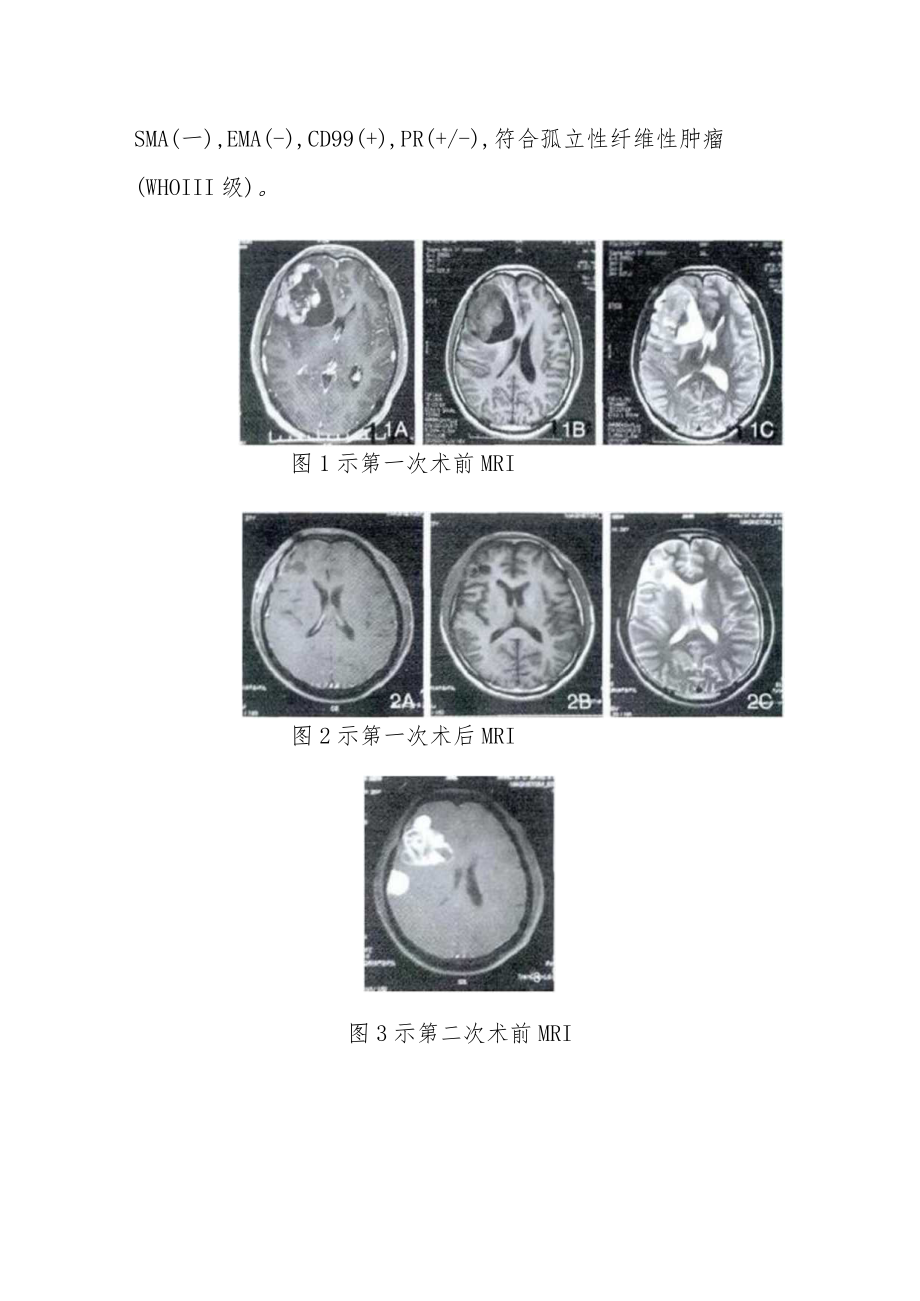

3、-IOO(灶+),SMA(一),EMA(-),CD99(+),PR(+/-),符合孤立性纤维性肿瘤(WHOIII级)。图1示第一次术前MRI图2示第一次术后MRI图3示第二次术前MRI图4第二次术后MRI图5示第三次术前MRI讨论:2007年WHO中枢神经系统肿瘤分类将颅内孤立性纤维瘤归为脑膜组织肿瘤中的间叶肿瘤,而2016年新分类将其单独划为间叶性非脑膜上皮性肿瘤,但国内外关于颅内孤立性纤维瘤多为个案报道,因此关于孤立性纤维瘤的诊治研究尚需进一步研究。本病例报道显示肿瘤在头颅MRl上为平扫TlWI呈等、低信号,T2WI呈等、低及混杂信号,伴囊变及周围水肿,有占位效应,增强扫描显示肿瘤实质部分

2、提示右额叶异常信号,考虑孤立性纤维瘤术后复发;右侧额颈部异常信号,考虑脑膜瘤。术中见额叶病变呈灰红色,伴有囊变,囊液黄色,完整切除病变;见额颈部病变基底位于凸面硬膜,边界尚清,完整切除病变。术后病理提示(右侧额叶、顶叶、颗叶)梭形细胞肿瘤,倾向于孤立性纤维腺瘤。患者因头痛头昏伴四肢乏力20余天于2016年月就诊,查体无异常,头颅MRl提示右颗叶异常信号。再次手术术中见肿瘤肉红色,分叶状,向皮层嵌顿生长,广基粘连于大脑凸面硬膜上,连同侵蚀硬膜完整切除肿瘤。术后病理提示(右额颗叶)梭形细胞肿瘤,免疫组化:BcL-2(+),CD34(-),Ki-67(+,约30%),Vim(+),GFAP(-),S